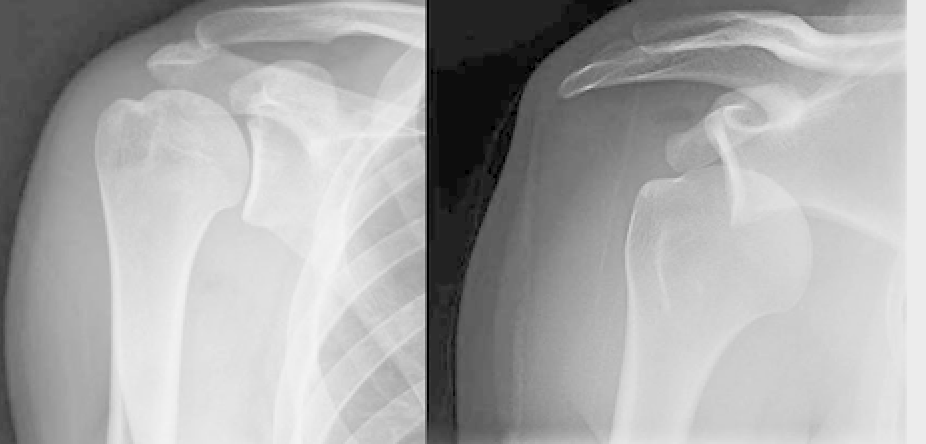

This person was pitching for softball when all of a sudden something didn't feel quite right and her arm was hanging a funny way... Which of the following best describes this shoulder injury?

Dislocation

This person was at football practice and dropped a barbell as they were doing bench presses on heavy weight day. Which of the following best describes this clavicle injury?

Transverse